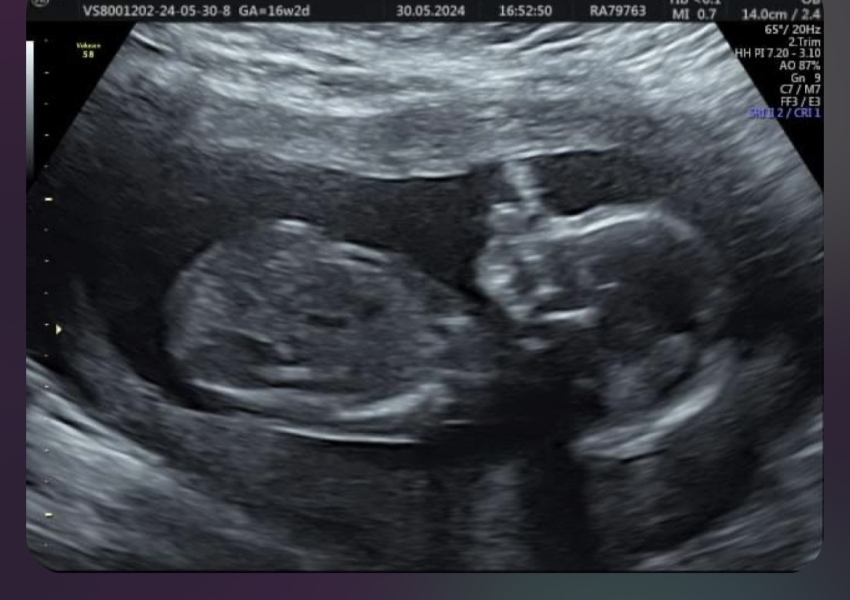

Jas2134 · 30/05/2024 23:09

can someone look at this please, this is my second child which I found out is another boy. I am happy of course , but I wanted a girl so bad. I had this scan at 16 weeks window to the womb, could it be wrong ?